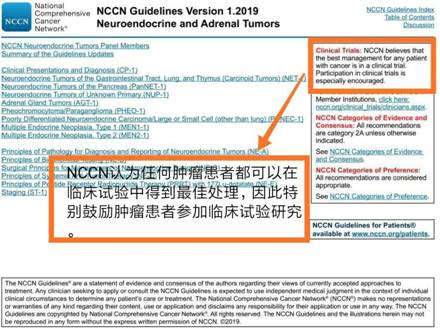

因为国际上最权威最广泛采用的癌症治疗指南——美国国立综合癌症网络(NCCN)在其指南中明确提出:NCCN认为任何肿瘤患者都可以在临床试验中得到最佳处理,因此特别鼓励肿瘤患者参加临床试验研究。